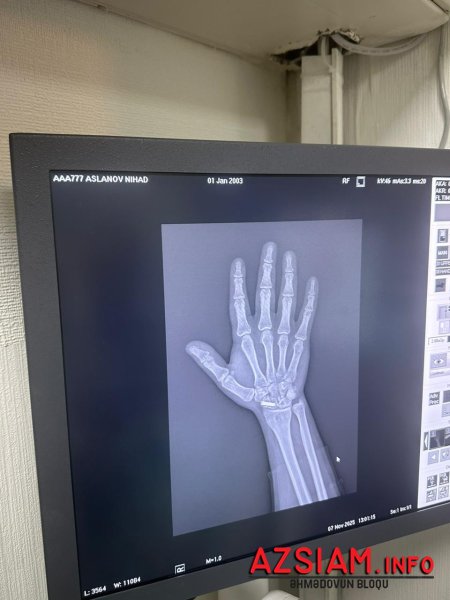

N.Aslanovun sözlərinə görə, universiteti bitirdikdən sonra Səfərbərlik Xidmətinin Rayon Şöbəsinə müraciət edib və könüllü xidmət etmək istəyini bildirib. Lakin 2022-ci ildə keçirdiyi ağır əməliyyat nəticəsində sağ biləyinə yerləşdirilən daimi mil ciddi problem yaradıb.

“Nizami Tibb Mərkəzi, Travmatologiya İnstitutu və hərbi komissarlığın (Red- Səfərbərlik Xidmətinin) öz həkimləri qolumdakı milə və funksiya pozuntusuna görə məni hərbi xidmətə yararsız hesab ediblər. Əməliyyat edən həkimim Zahid Cəfərovun diaqnozuna görə, mən 5 kiloqramdan artıq yük qaldıra bilmərəm, soyuq havada qolum sızıldayır və barmaqlarımın hərəkəti məhduddur. Əlim silah tutacaq vəziyyətdə deyil”,-deyə çağırışı Nihat Aslanlı bildirib.

DSMF ilə ziddiyyət: “6 aylıq möhlət verdilər ki, mili çıxartdırım”.Vətəndaş bildirir ki, Səfərbərlik Xidmətinin hərbi həkim komissiyası onun işini rəy üçün Sosial Müdafiə Fonduna göndərib. İlkin yoxlanışda ona 6 aylıq möhlət verilib və bildirilib ki, müddət bitdikdən sonra hərbi biletini ala bilər. Lakin müddət bitdikdən sonra vəziyyət köklü şəkildə dəyişib.“6 ay sonra yenidən yoxlanışa çağırdılar. Bu dəfə Səfərbərlik Xidməti mənə bildirdi ki, biz səni yararsız yazsaq da, Sosial Müdafiə Fondu bizim rəyimizin üstündən xətt çəkərək səni yararlı hesab edib. Səbəb kimi isə göstərirlər ki, guya mənə o 6 ayı qolumdakı mili çıxartdırmaq üçün veriblər. Hansı ki, o mil ömürlükdür və sümük hələ də bitişməyib. Mili çıxartmaq əlimin tamamilə iflic olması deməkdir”.